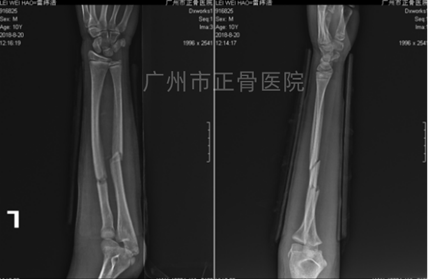

治疗:运用正骨手法复位后小夹板外固定治疗。复查X线片提示骨折端对位对线较前明显改善,目前位置良好。定期复查换药,拍摄X线了解骨折情况。4周后复查X线提示折端稳定,骨痂较多,指导患者循序渐进进行功能康复锻炼。9周后拆除外固定,指导患者加强功能康复锻炼。10周后复查,肘、腕关节活动基本恢复正常,患处无压痛。

▲复位后,骨折端对位对线改善